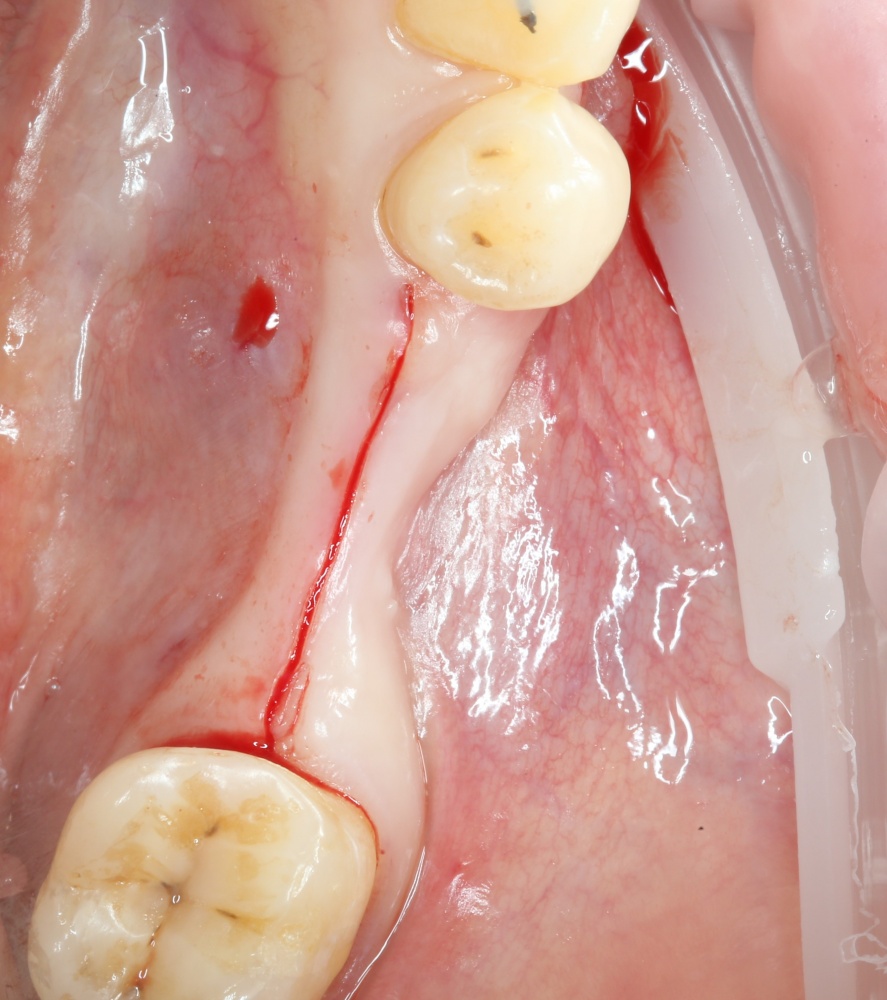

Операция начинается с разреза. Напомню, что разрез делается в пределах прикрепленной десны, это важно для последующего соблюдения Фактора успеха III:

A09A5444 (2)

Конечно, было бы легче сделать разрез по подвижной слизистой оболочке, но в последующем такой шов легко расходится и создать полную герметичность будет сложно.